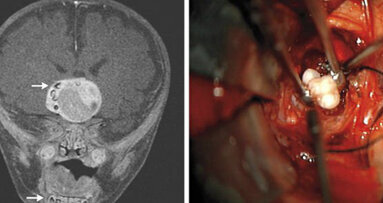

BALTIMORE, USA: Alcuni neurochirurghi negli Stati Uniti hanno trovato denti completamente formati all'interno di una massa tumorale che stava crescendo nel ...